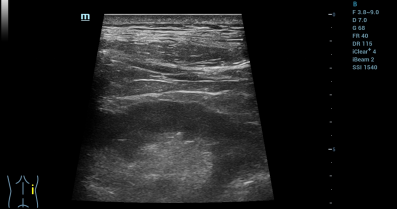

细胞移植环节采用“肾脏专科+超声影像专科”联合诊疗模式,实施超声实时引导下精准肾内靶向注射。操作者在术前对患者进行细致的双肾影像学评估,在超声实时观察下精准测算肾脏皮质厚度、肾动脉内径及解剖走向,规划最优进针角度与安全路径。术中采用局部微创麻醉,在超声定位给药点进针,实时引导患者呼吸节律调控,规避脏器牵拉风险。在超声仪探头实时检测的同时,经皮精准穿刺至肾实质中带定位给药,靶向富集于肾损伤区域。

9 X' s" f# f* X6 J: `5 L/ s  细胞移植完成后结合CDFI彩色血流成像复核,确认给药位点精准、无活动性出血及肾周渗漏。患者术中全程清醒耐受良好,无即时不良反应。细胞移植后0天至3天短期随访数据显示,患者生命体征平稳、自主活动正常,无感染、发热及注射并发症。细胞移植后3天患者总蛋白、白蛋白指标由术前长期低于正常值水平(分别为60.4 g/L和37.8 g/L)提升至正常水平(65.2 g/L和40.9 g/L),短期内初步验证了给药安全性与修复疗效。% B( Q1 v! J5 L3 O) c0 d5 _2 [

术后超声复查,示肾周及集合系统结构清晰,未见异常征象。